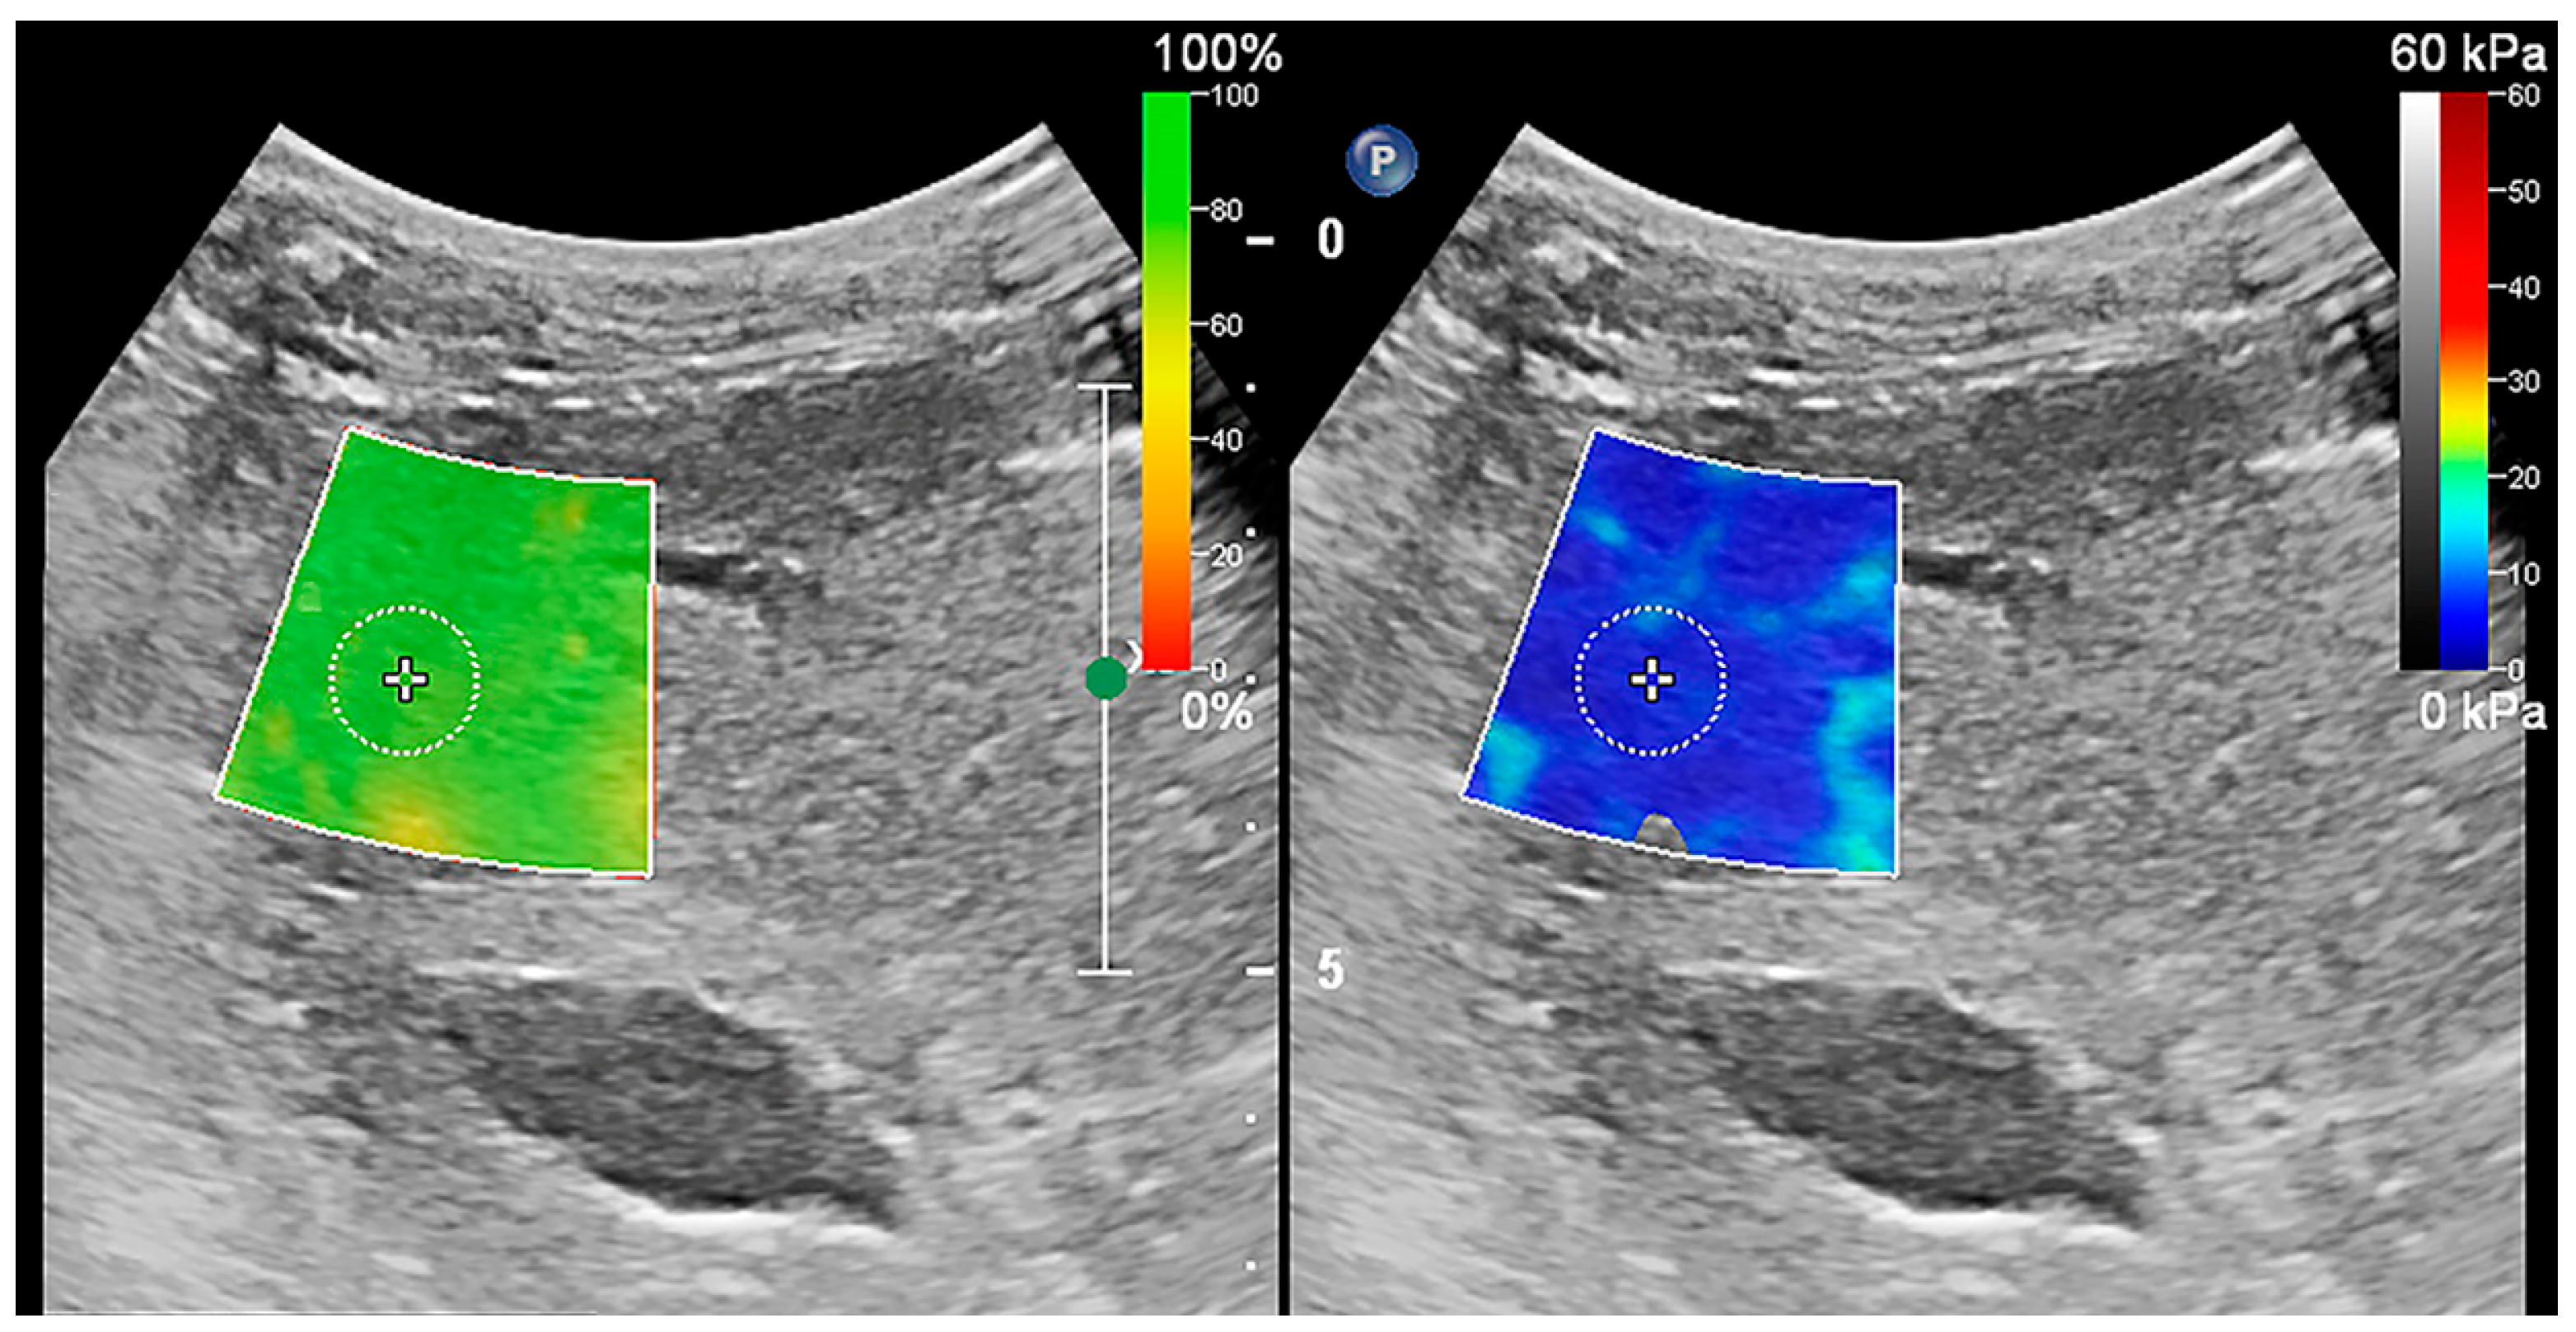

To maintain uniformity in measurement results, the ultrasound parameters for 2D-SWE were set to the system’s default configuration and no adjustments were made during the measurement process. The dual-screen mode of 2D-SWE was selected on the ultrasound machine, which displayed the confidence map on the left and the stiffness map on the right. The confidence map converted the confidence level of the measurements into different colors, which were overlaid on the ultrasound greyscale map. Green was regarded as highly reliable data, while red indicated unreliable data. The stiffness map represented tissue stiffness, with blue and red indicative of the lowest and highest stiffness, respectively (Figure 1). The absence of a color overlay on the stiffness map suggested that the measured value had a low confidence level that could not be measured. A 2 × 2 cm fan-shaped elastic sampling frame was placed over the target tissue in B-mode images. The intrusion depth was 5 cm, and the sampling frame was set at a minimum of 10 mm below the liver capsule to avoid possible reverberation artifacts. Then, a circular ROI of 10 mm diameter was placed in the flexible sampling frame. Care was taken when placing the elastic sampling frame and ROI to avoid blood vessels, bile ducts, and other membranous structures. The ROI placement also needed to meet additional two requirements. First, the color needed to remain stable on the stiffness map for a few seconds. Second, it needed to be green on the confidence map. After placing the ROI, the average, median, maximum, and interquartile range to the median ratio (ICR/MED) of stiffness within the ROI area were measured. According to the liver elastography guidelines originally developed from TE in human medicine, only an ICR/MED less than or equal to 30% was considered statistically significant, and the average represented the stiffness of the tissue within the ROI [5,30]. Tissue stiffness was measured as SWV, which was automatically converted to Young’s modulus by an embedded software package.

Figure 1. Shear wave elastography of the liver. Confidence map mode was on the left and stiffness map mode was on the right. In the confidence map mode, confidence levels were converted from low to high as red, yellow, and green. In the stiffness map mode, the liver stiffness was converted from low to high as blue, yellow, and red. The elastic sampling frame and ROI were placed to ideally avoid the vessels, bile ducts, and liver envelope, and the ROI was placed in the green position on the confidence map.